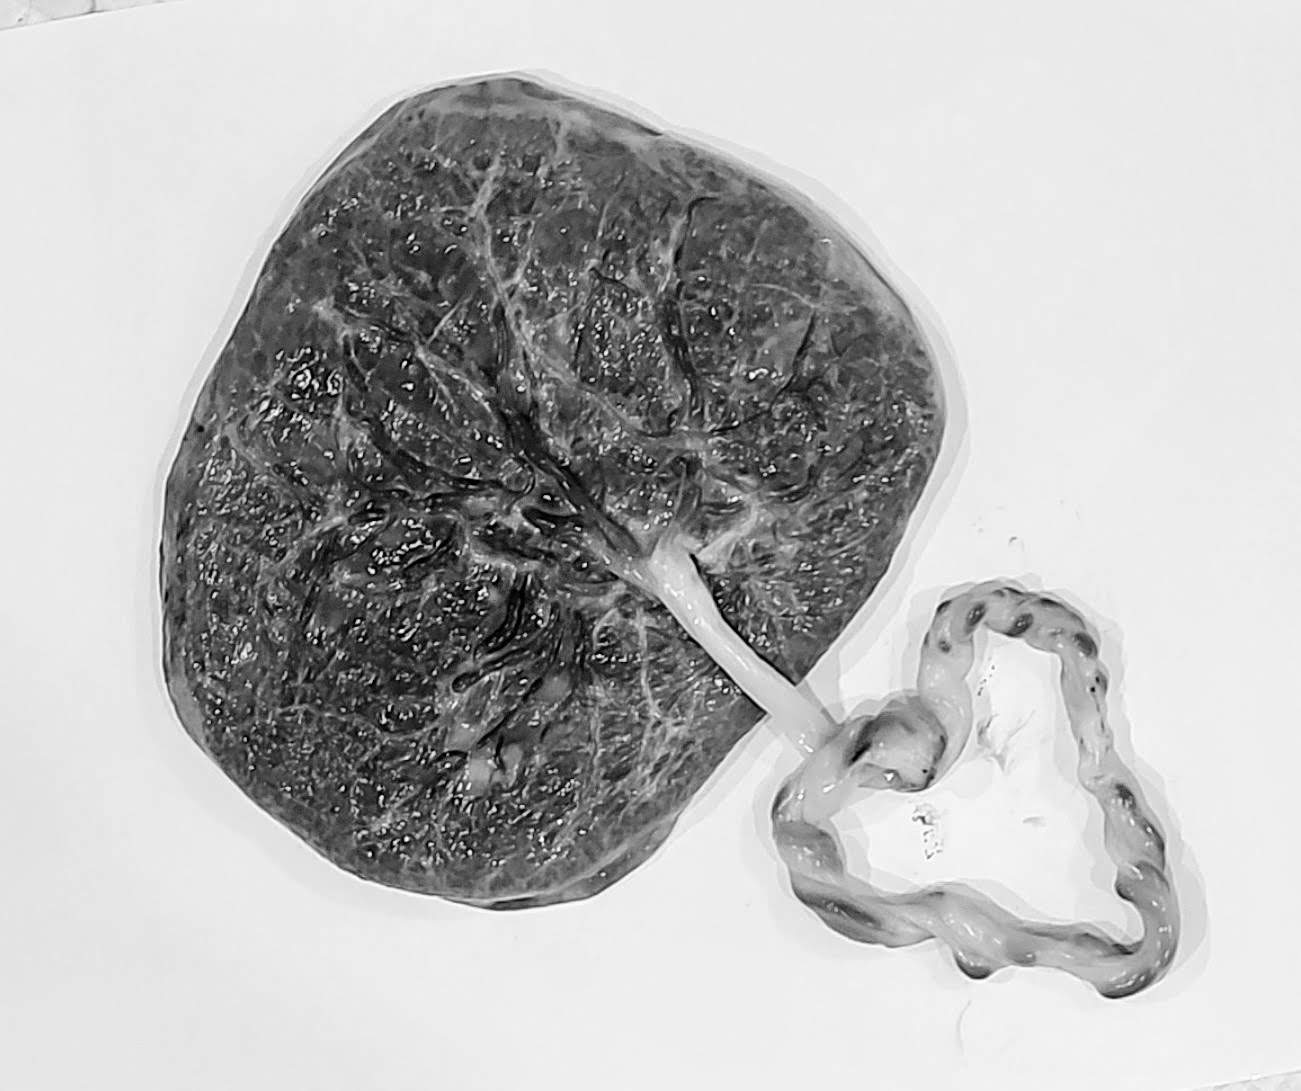

Our Placenta Services/Products include: Placenta Pills/Powder, Placenta Tinctures, 3 unique Placenta Smoothie options, Placenta Energy Bites, Placenta Chocolates, Placenta Gummies (coming soon!), Placenta-Infused Broth, Umbilical Cord Keepsakes, artistic Placenta Prints, and Herbal Healing Butters for Mom & Baby! And, for the woman who wants it all, there is even a Bundle & Save Package that offers everything at a discounted price!